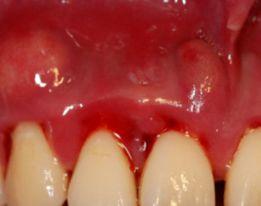

口腔中有没治疗的龋齿、残根、残冠、不良修复体、牙龈炎、牙周炎及口腔粘膜病等都可以引起口臭。

牙周炎患者常伴有大量的牙石、菌斑,牙周袋内细菌发酵产生硫化氢、吲哚和氨类,也会产生臭味;

牙周脓肿和牙周袋溢脓,多为金黄色葡萄球菌合并牙周致病菌感染,也会发出臭味;